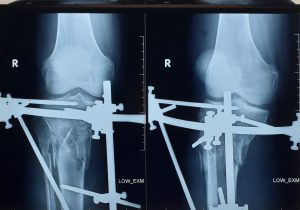

??PHẪU THUẬT THÀNH CÔNG CỨU SỐNG BỆNH NHÂN ĐA CHẤN THƯƠNG DO TAI NẠN GIAO THÔNG KHÔNG CÓ NGƯỜI NHÀ.

Vừa qua BVĐK Xuyên Á tiếp nhận trường hợp bệnh nhân Nam 41t với tình trạng bệnh lơ mơ, kích thích đau đáp ứng, trên người có mùi rượu. Qua khai thác ban đầu từ người đưa BN đến cấp cứu được biết bệnh nhân chạy xe máy bị xe tải đụng được sơ cứu […]